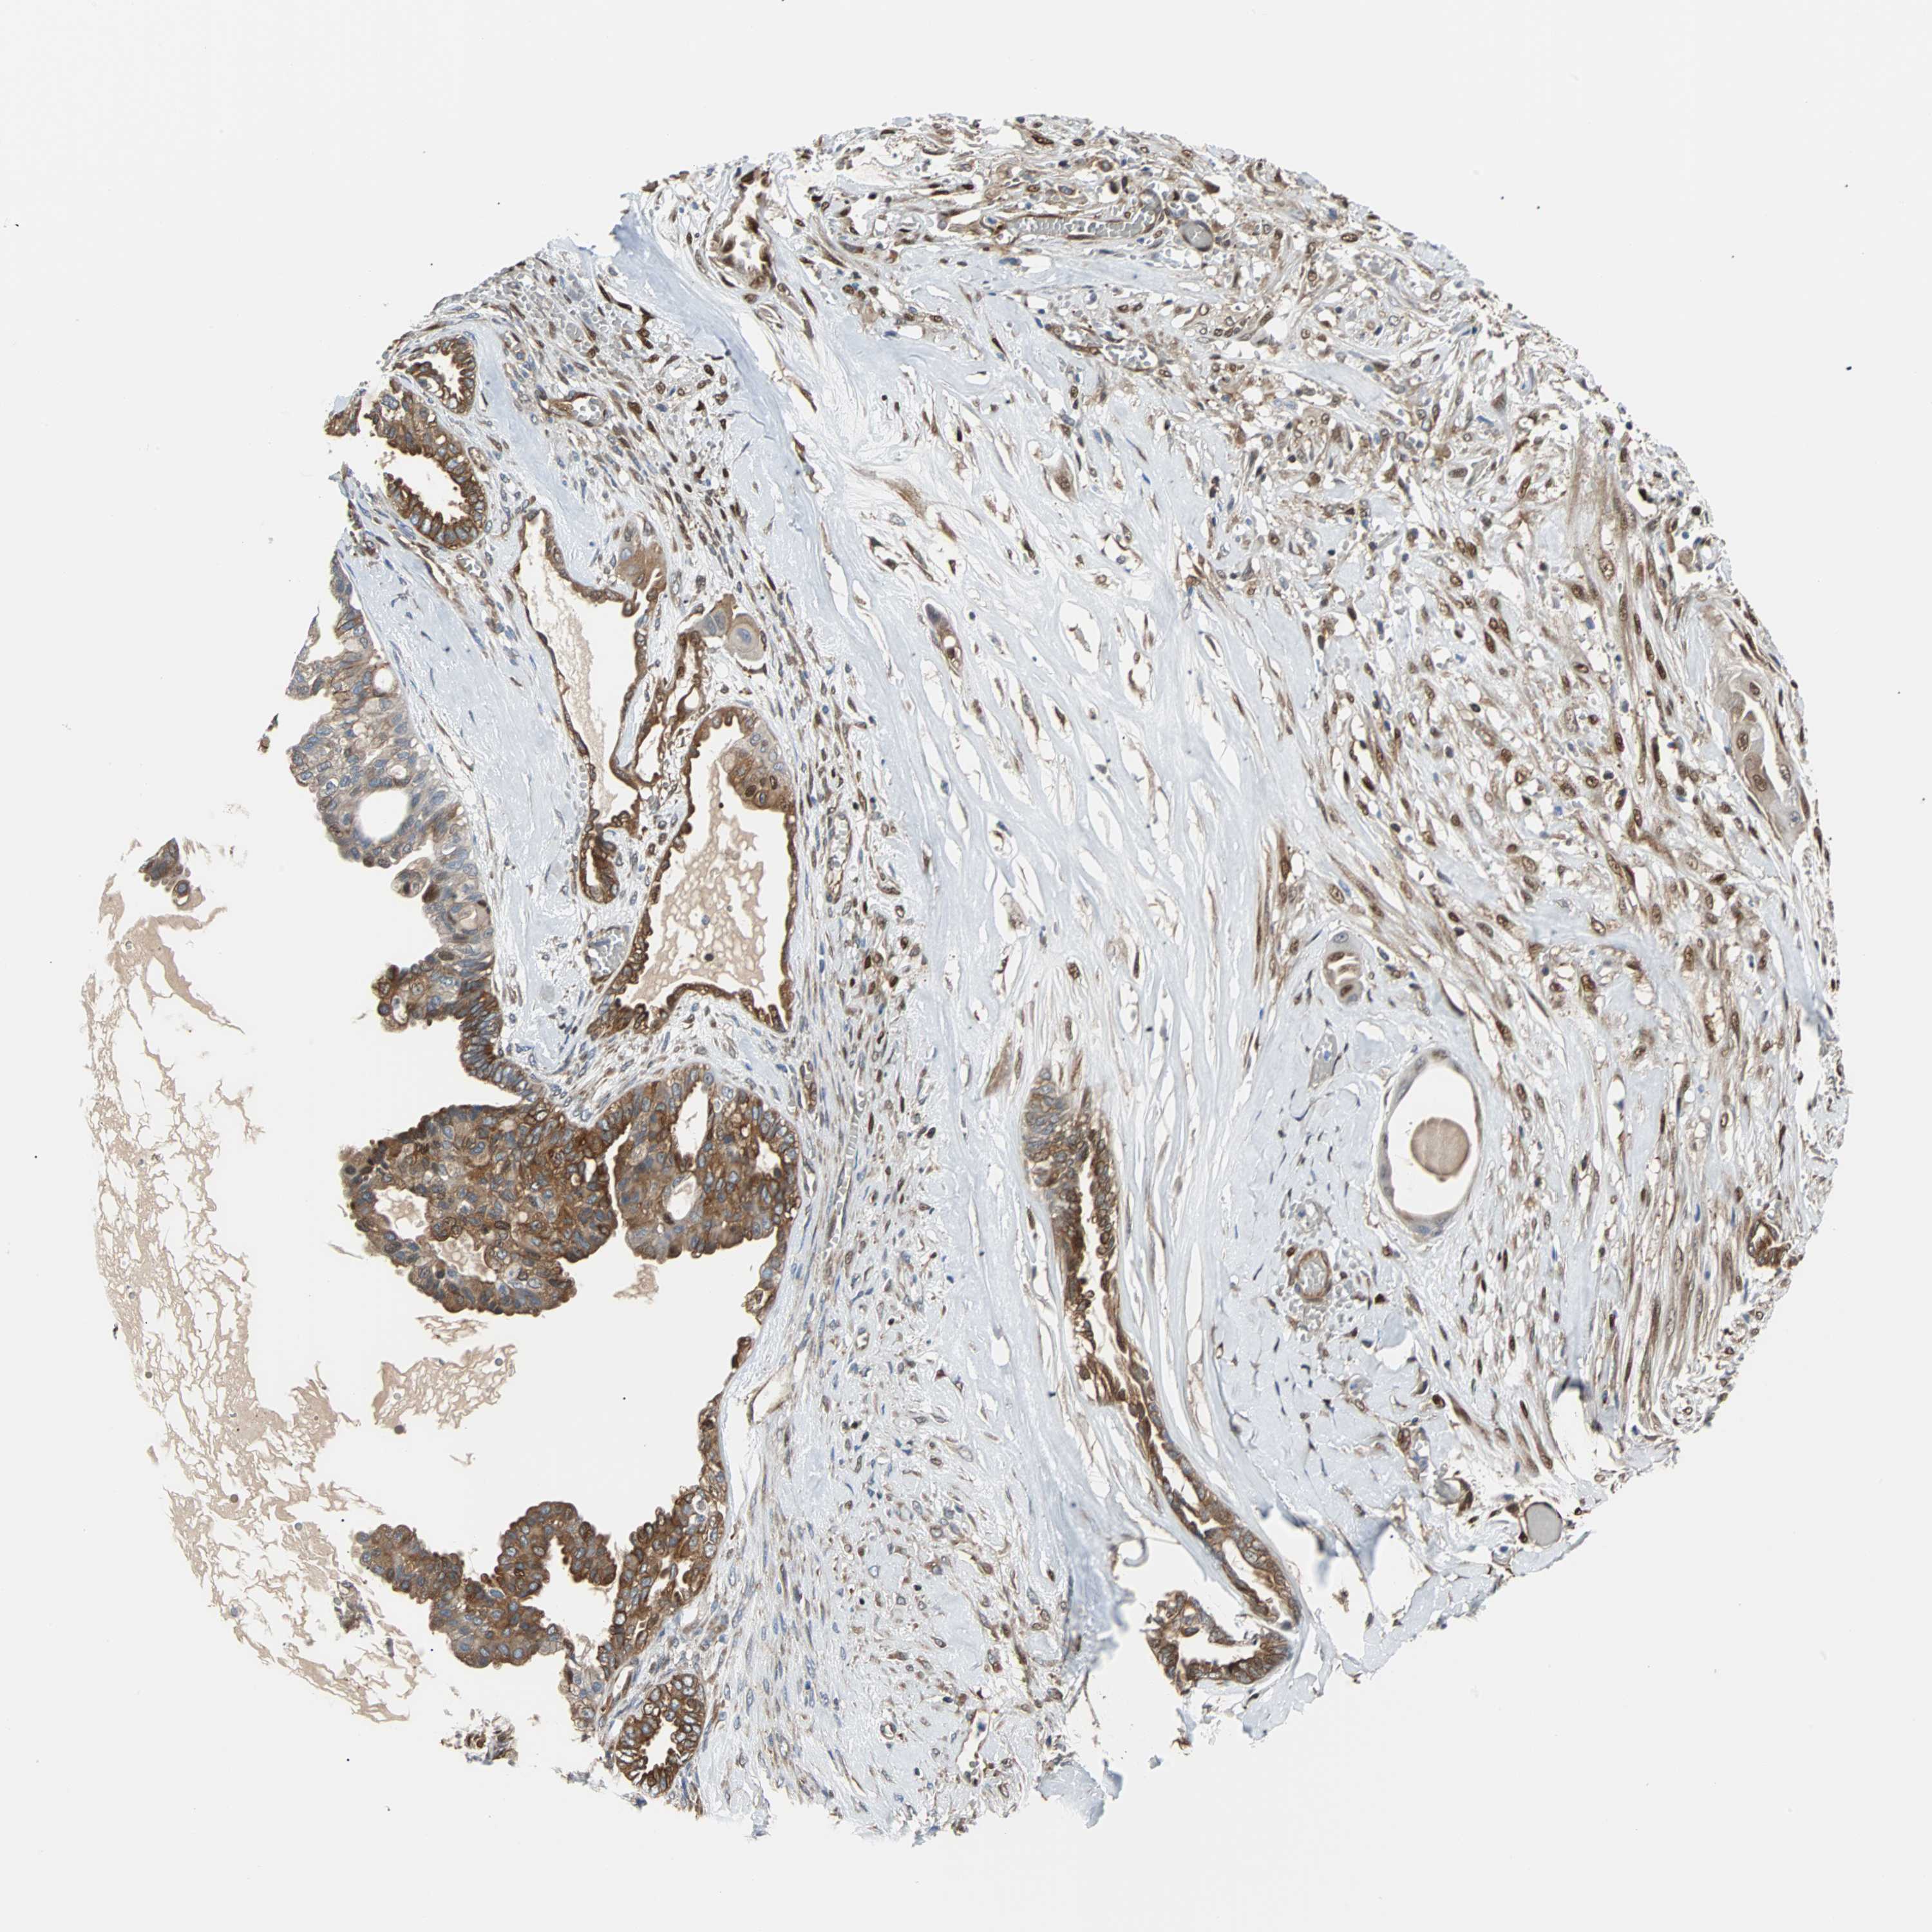

OVARIAN CANCER - Protein expressioni

A mouse-over function shows sample information and annotation data. Click on an image to view it in a full screen mode. Samples can be filtered based on level of antibody staining by selecting one or several of the following categories: high, medium, low and not detected. The assay and annotation is described here.

Note that samples used for immunohistochemistry by the Human Protein Atlas do not correspond to samples in the TCGA dataset.

Antibody stainingi

Antibody staining in the annotated cell types in the current human tissue is reported as not detected, low, medium, or high, based on conventional immunohistochemistry profiling in selected tissues. This score is based on the combination of the staining intensity and fraction of stained cells.

Each image is clickable and will lead to virtual microscopy that enables deeper exploration of all samples and also displays staining intensity scores, fraction scores and subcellular localization as well as patient and tissue information for each sample.

Antibody CAB004264

Antibody CAB005030

Staining

High

Medium

Low

Not detected

Intensity

Strong

Moderate

Weak

Negative

Quantity

>75%

75%-25%

<25%

None

Location

Nuclear

Cytoplasmic/membranous

Cytoplasmic/membranous,nuclear

Cystadenocarcinoma, serous, NOS

Carcinoma, endometroid

Carcinoma, NOS

Cystadenocarcinoma, mucinous, NOS